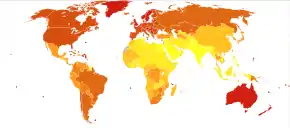

Melanoma is the most dangerous type of skin cancer.[2] Globally, in 2012, it newly occurred in 232,000 people.[2] In 2015, 3.1 million people had active disease, which resulted in 59,800 deaths.[5][6] Australia and New Zealand have the highest rates of melanoma in the world.[2] High rates also occur in Northern Europe and North America, while it is less common in Asia, Africa, and Latin America.[2] In the United States, melanoma occurs about 1.6 times more often in men than women.[13] Melanoma has become more common since the 1960s in areas mostly populated by people of European descent.[2][11]

Possible significant elements in determining risk include the intensity and duration of sun exposure, the age at which sun exposure occurs, and the degree of skin pigmentation. Melanoma rates tend to be highest in countries settled by migrants from Northern Europe which have a large amount of direct, intense sunlight to which the skin of the settlers is not adapted, most notably Australia. Exposure during childhood is a more important risk factor than exposure in adulthood. This is seen in migration studies in Australia.[31]

Globally, in 2012, melanoma occurred in 232,000 people and resulted in 55,000 deaths.[2] Australia and New Zealand have the highest rates of melanoma in the world.[2] It has become more common in the last 20 years in areas that are mostly Caucasian.[2]

Australia has a very high – and increasing – rate of melanoma. In 2012, deaths from melanoma occurred in 7.3–9.8 per 100,000 population. In Australia, melanoma is the third most common cancer in either sex; indeed, its incidence is higher than for lung cancer, although the latter accounts for more deaths. It is estimated that in 2012, more than 12,000 Australians were diagnosed with melanoma: given Australia's modest population, this is better expressed as 59.6 new cases per 100,000 population per year; >1 in 10 of all new cancer cases were melanomas.[153] Melanoma incidence in Australia is matter of significance, for the following reasons:

- Australian melanoma incidence is, by some margin, the highest in the world.

- Overall age-standardized cancer incidence in Australia is the highest in the world, and this is attributable to melanoma alone. Age-standardized overall cancer incidence is similar to New Zealand, but there is a statistically significant difference between Australia and all other parts of the developed world including North America, Western Europe, and the Mediterranean.